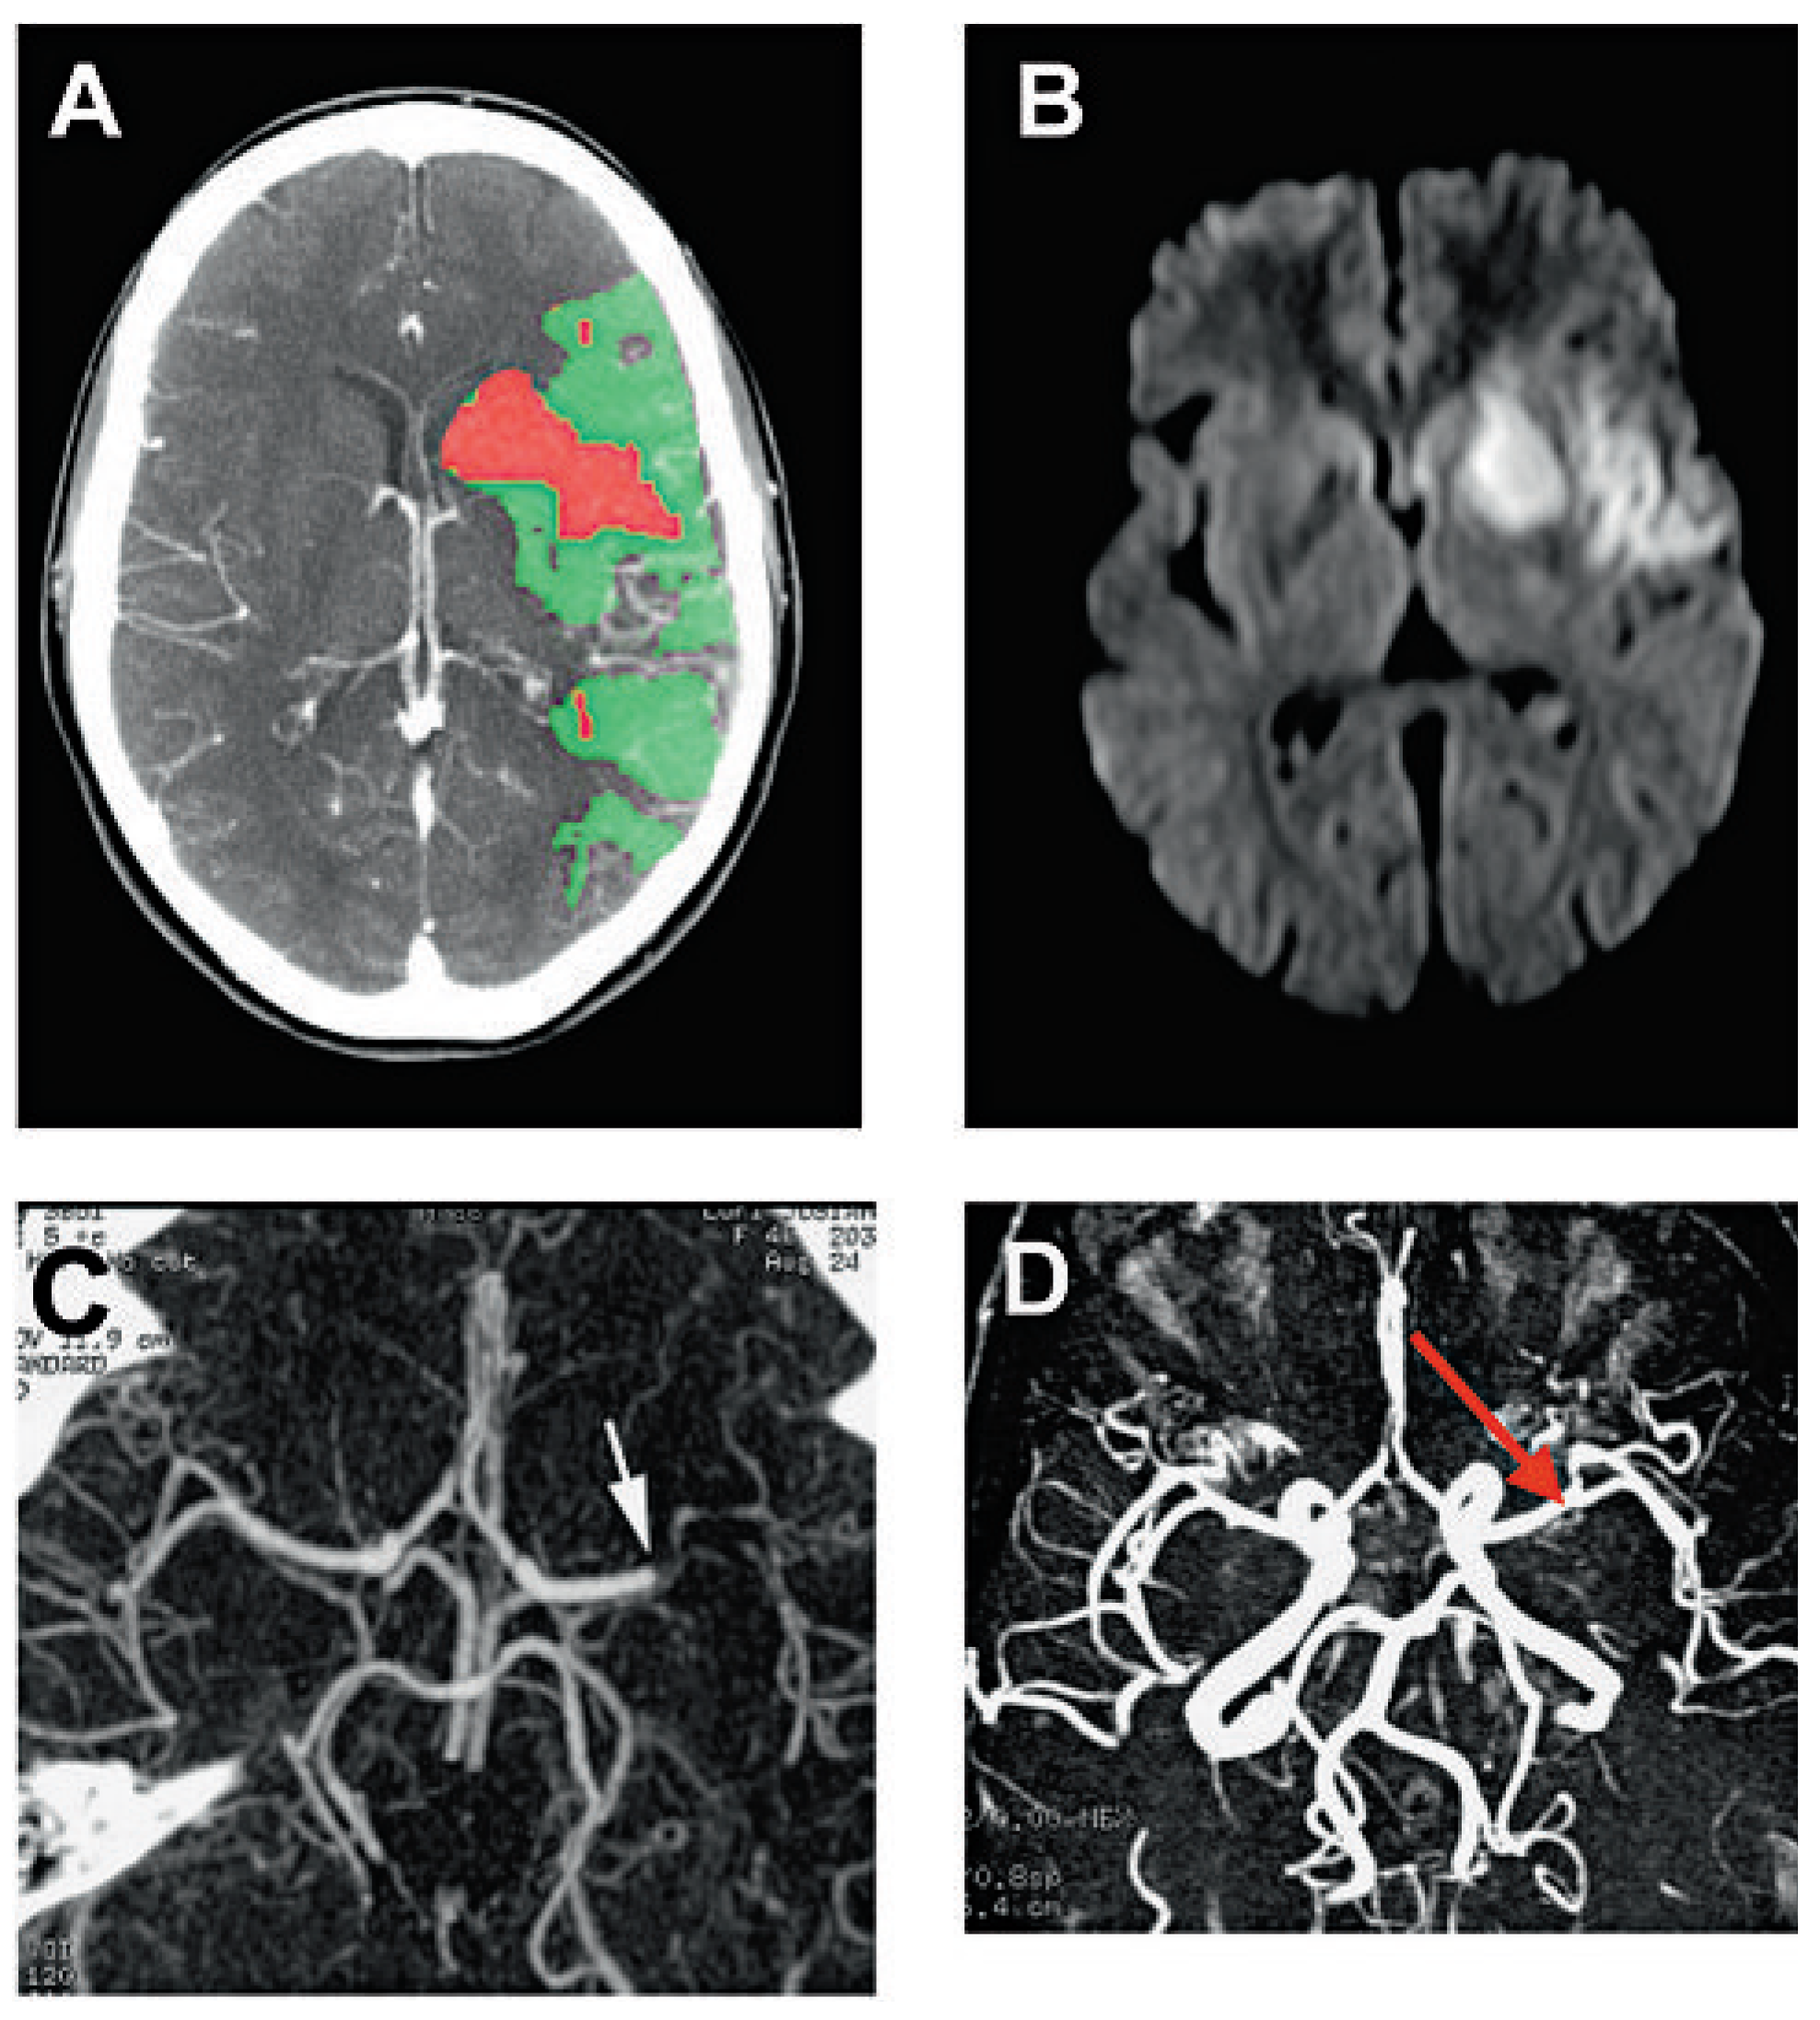

![]() |